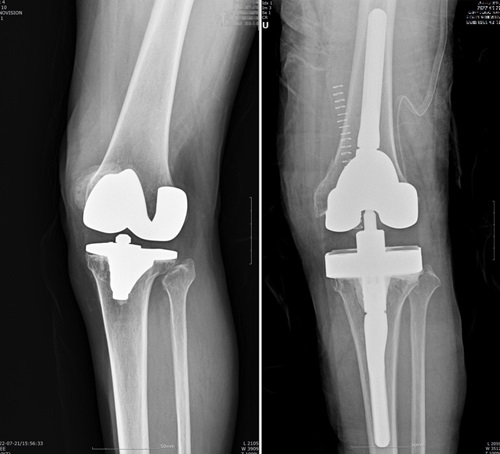

인공관절 재치환술은 빙판길 낙상사고 등 외상으로 문제가 생기거나, 인공관절을 오래 써서 닳아 흔들리거나 염증‧감염으로 인해 인공관절이 제 기능을 하지 못하고 통증을 일으킬 때 하는 수술이다.

재치환술은 골 소실 및 연부조직 손상을 동반하기 때문에 수술 자체도 까다롭고 처음 수술보다 결과가 좋지 않은 경우가 많다. 80세 이상의 고령 환자가 많아 만성질환 합병증의 위험도 따른다. 실제 통계에 따르면 인공관절 재수술을 받은 환자 809명 중 80세 이상이 16%를 차지했다.

인공관절은 대략 15년에서 최장 25년의 수명을 갖는다. 때문에 정형외과 전문의들이 너무 젊은 나이에 인공관절 수술하기보다 가급적 65~70세 사이에 한 번만 수술을 받을 것을 권장한다. 특히 인공관절 재치환은 골 소실과 연부조직 손상을 동반하는 만큼 수술 자체도 까다롭고, 처음 수술보다 결과가 좋지 않을 수 있다.

연세사랑병원(정형외과 전문의) 고용곤 원장은 “100세 시대가 도래하며 인공관절 수술을 한 번 더 해야 하는 상황이 벌어지고 있다. 인공관절의 수명이 대략 15년에서 최장 25년으로 늘어났지만, 사람의 수명 역시 계속해서 늘고 있기 때문”이라며 “인공관절 재치환술은 1차 수술에 비해 까다롭고 시간도 오래 걸리는 수술이라 의료진의 실력에 따라 천차만별의 결과를 낳기 때문에 의사의 임상 경험이 풍부한지, 병원이 전문재치환술센터를 갖고 있는지 등을 따져보는 것이 좋다”고 조언했다.